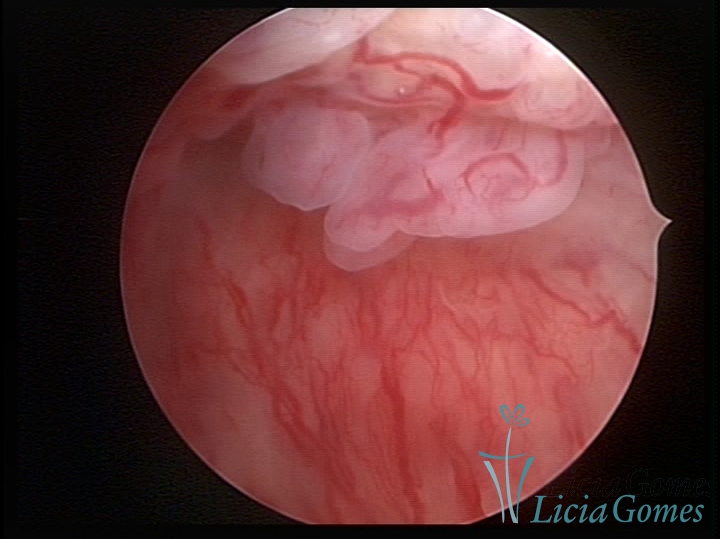

ENDOCERVICAL POLYPS

Benign tumors resulting from the reactive focal proliferation to inflammatory processes or hyperestrogenism situations, which may be sessile (with a large implantation) or stalked.